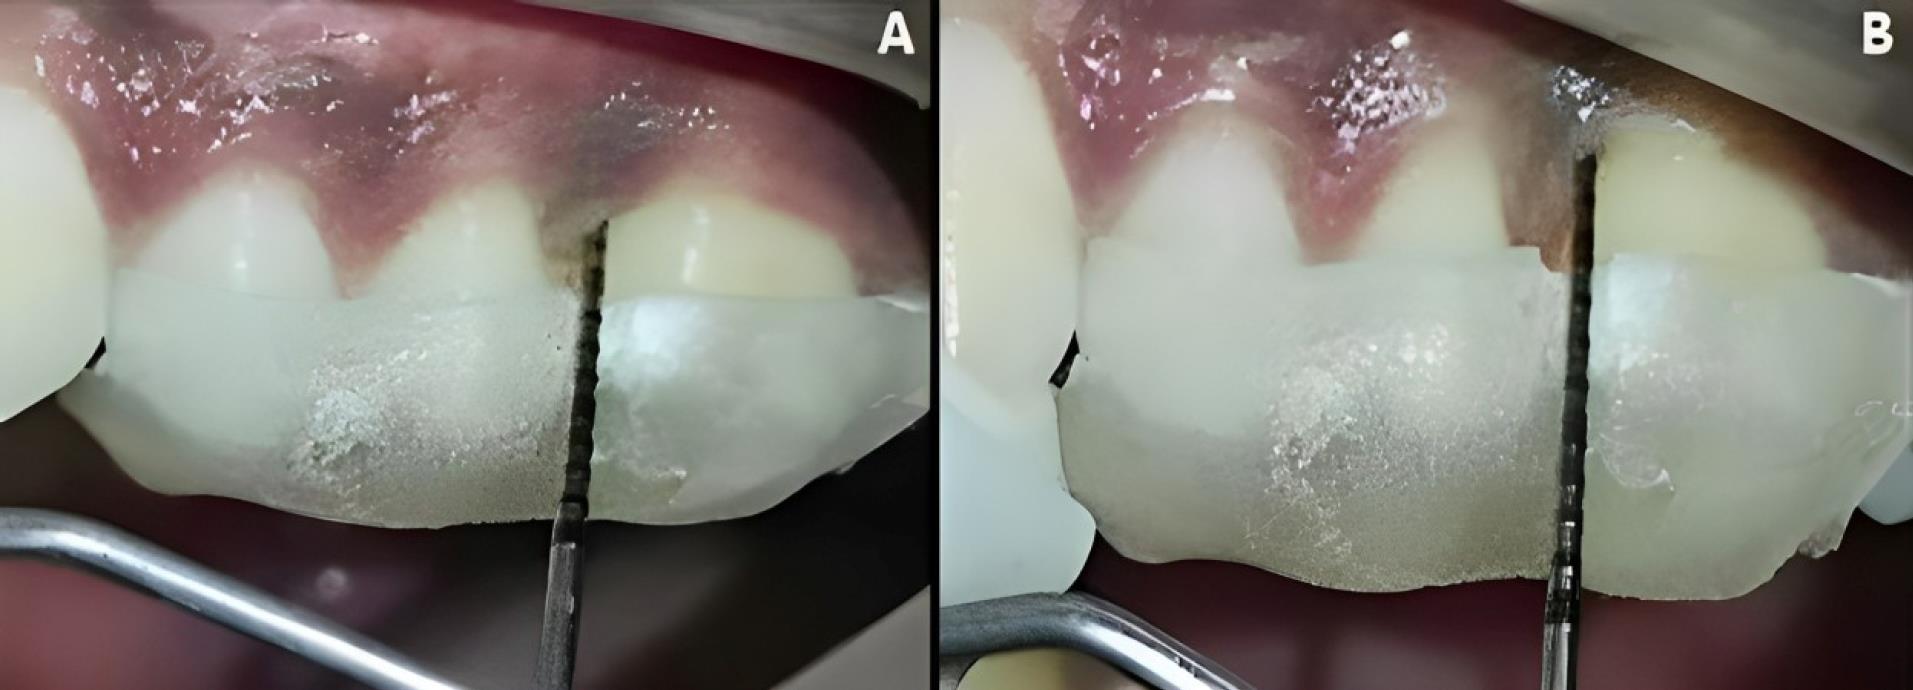

At experimental site A, after OFD and defect exposure, using 3-0 absorbable sutures, a pre-suturing procedure was carried out before the CGF membrane placement. Then, the defect was covered with a CGF membrane, as shown in Figure 3. At experimental site B, following OFD, the defect area was irradiated with a diode laser of 810 ± 20-nm wavelength at a power output of 1 W in contact, continuous mode through an optic fiber of 400 µm for 30 seconds intermittently (10 seconds/irradiation) in a parallel manner and sweeping motion from coronal to apical part and another application with the same wavelength of the laser used before, but in a non-contact, continuous mode at 0.5 W was used resulting in a complete dose of 4 J/cm2/surface on the inner surfaces of the flap and also on the surfaces of the intrabony defect. After laser irradiation, the defect was covered by a CGF membrane, with prior pre-sutures placed, as shown in Figure 4.

Figure 4.

Surgical procedure in experimental site B. A. Preoperative. B. Intrabony defect exposure. C&D. Diode laser application. E. CGF membrane placement. F. Suture placement. G. Periodontal dressing placement. (CGF: concentrated growth factor)

Figure 6.

Experimental site B, postoperative-clinical. A. 3 months. B. 6 months